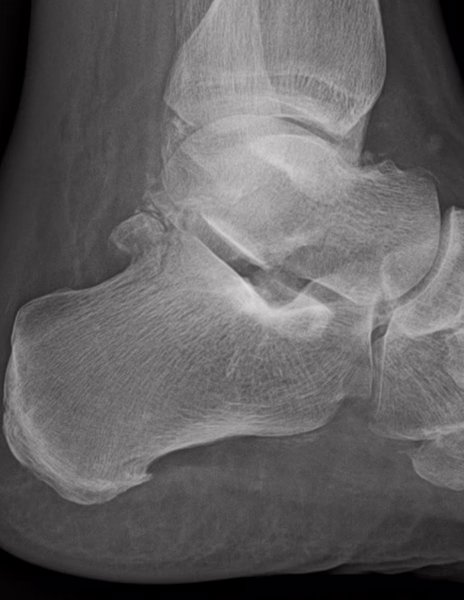

RADIOGRAFIA AP Y LATERAL DE TOBILLO

-Existe fractura a nivel de proceso posterior de astrágalo con involucro de porción superior del calcáneo. Existe espícula osteofítica en porción inferior de tuberosidad del calcáneo. Resto de huesos del tarso y metatarsos, sin evidencia de lesiones líticas, blásticas o perdida de la contigüidad.

-Angulo de Bohler de 53.1 °

OPINIÓN RADIOLÓGICA:

EN EL PRESENTE ESTUDIO RADIOGRÁFICO, EXISTE FRACTURA DEL PROCESO POSTERIOR DEL ASTRÁGALO E INVOLUCRO SUPERIOR DEL CALCÁNEO, CON EDEMA ASOCIADO.